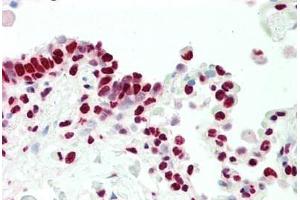

• 图像